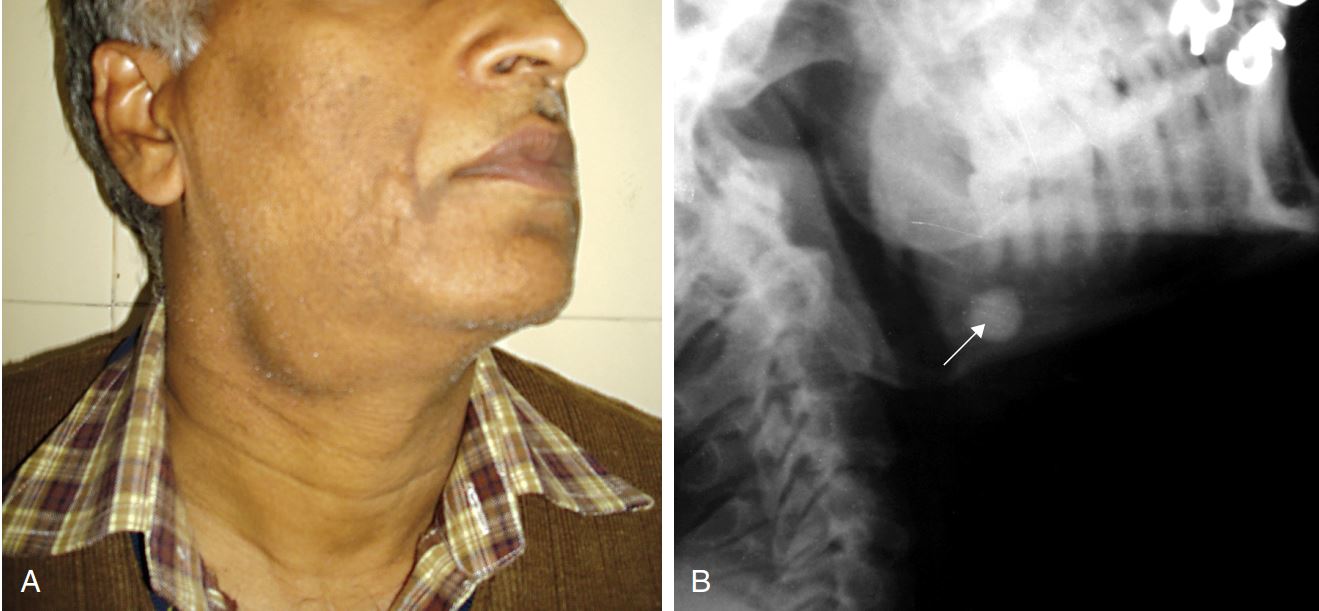

PS. 下圖是最近來本院所就診的患者,他的結石在近口端已經多年的歷史,經過處置幫病人把結石順利取出